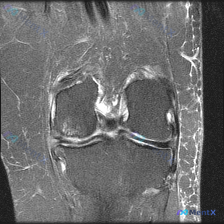

单张膝关节冠状位MRI:看到股骨外侧髁信号异常,不止软骨问题这么简单

今天看到这份单张膝关节冠状位MRI(T2加权+脂肪抑制),问题指向「软骨异常」,整理了完整的分析思路分享给大家。

这是单张冠状位的膝关节MRI图像,核心异常发现如下:

- 骨骼软骨:股骨外侧髁关节面下骨髓可见范围较广、边界模糊的片状高信号,提示骨髓水肿;股骨内侧髁、胫骨平台骨髓信号均匀,无明确骨折线或囊性变

- 半月板:内外侧半月板体部信号大致正常,无明显移位撕裂碎片,但单层冠状位对细微撕裂评估有限

- 韧带软组织:可见外侧副韧带走行区,髁间窝可见交叉韧带断面(冠状位不是观察交叉韧带最佳层面),关节腔内可见少量积液

- 核心病变定位:股骨外侧髁软骨下骨,为弥漫片状高信号,累及负重区